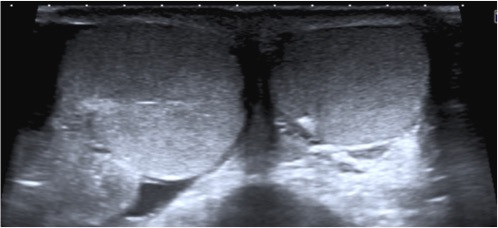

Testu00edculos asimu00e9tros en un corte axial en una imagen obtenida por en un ecu00f3grafo publicada por

Testículos asimétros en un corte axial en una imagen obtenida por en un ecógrafo publicada por radiodiagnosticando.com